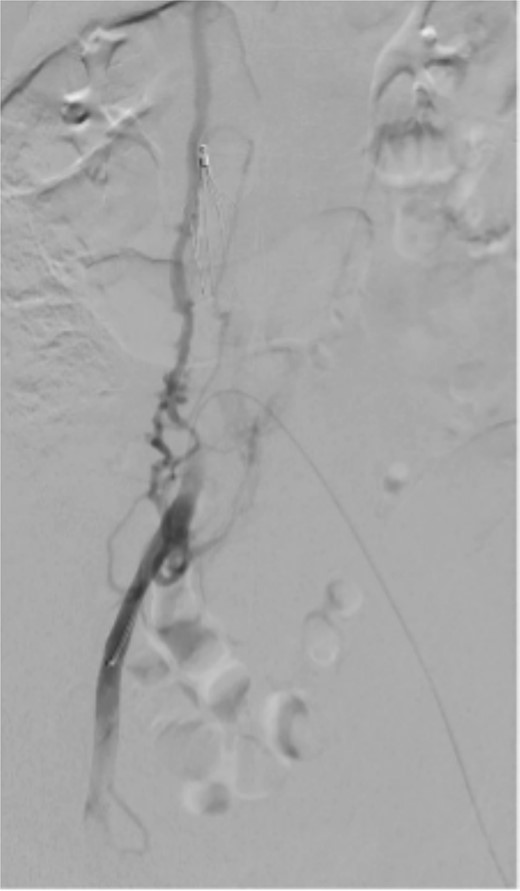

On postoperative Day 10, the patient complained of right lower limb swelling (Fig. 3). Ultrasound Duplex revealed acute thrombosis of her right common and external iliac veins. As pain and swelling increased overnight with prolonged CRT to 4 s, she underwent thrombolysis and stenting.

Following thrombolysis, stenting is often required to address underlying venous stenosis [3]. Although cases of successful bilateral iliac vein stenting have been reported, the initial focus was on saving the symptomatic limb. Given the patient’s narrow caval confluence and collateral drainage of her right lower limb (Fig. 3), we did not deploy ‘kissing’ stents initially.